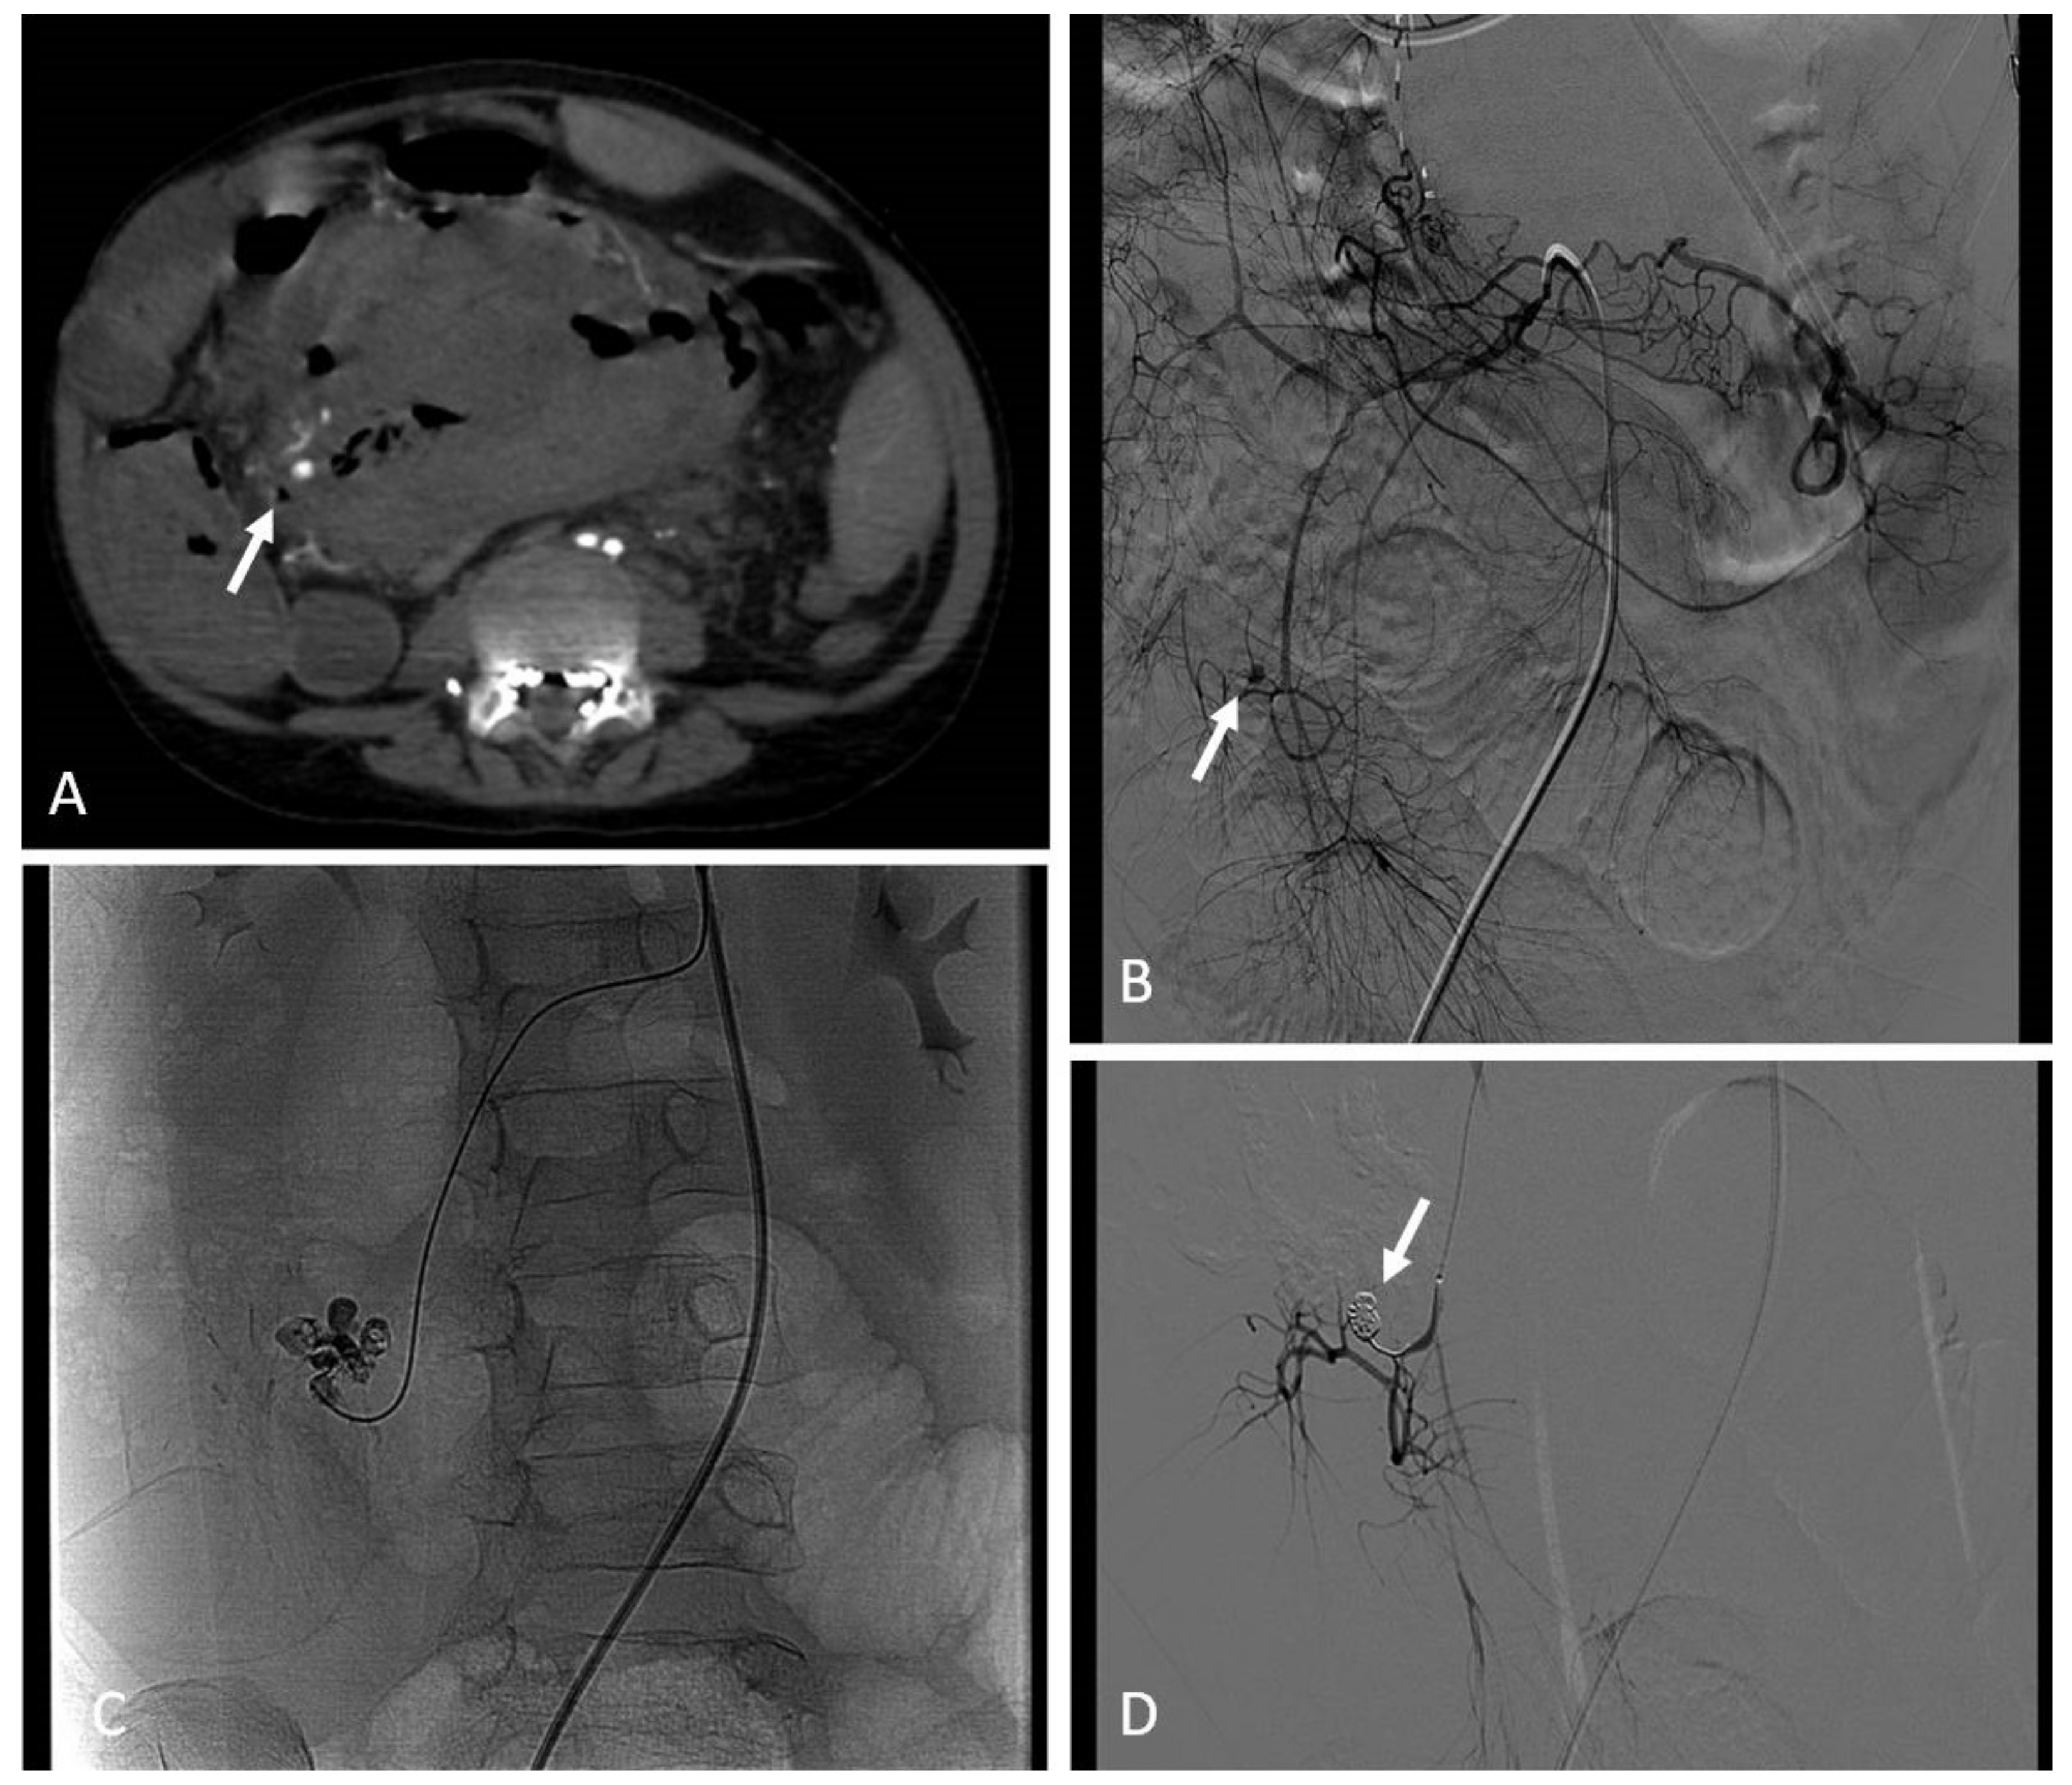

9. Arterial Aneurysms and Pseudoaneurysms

9.1. Indications

9.2. Techniques

9.3. Clinical Outcomes